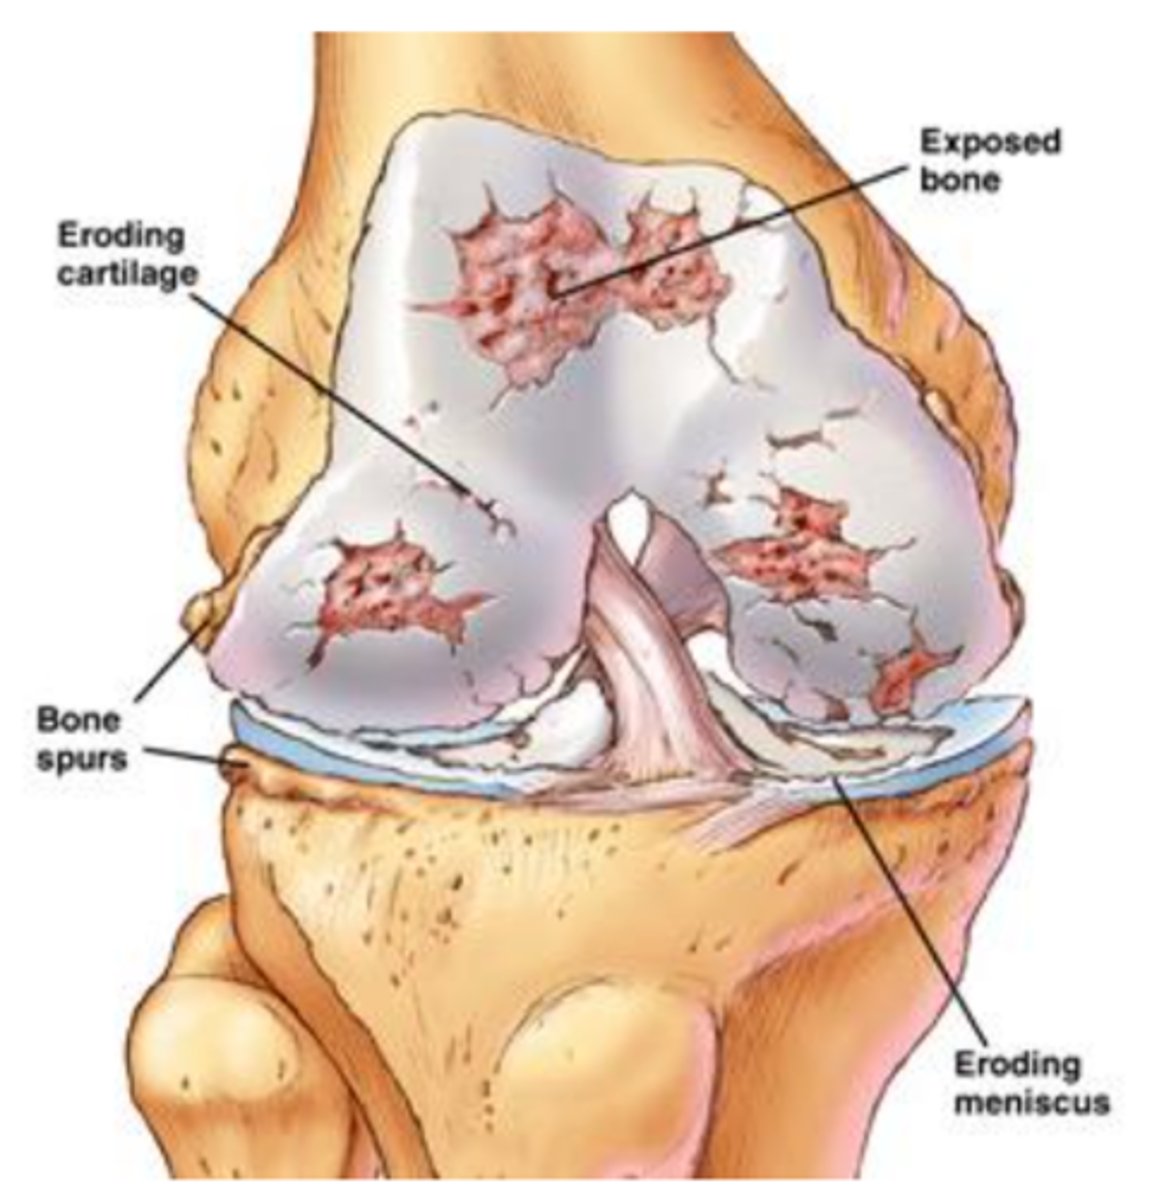

eroding cartilage

cartilage

osteoarthritis (image)

What symptoms can you see on an x-ray?

bone spurs, narrowing space

radiograph "LOSS"

a. Loss of joint space

b. Osteophytes - spurs of bone